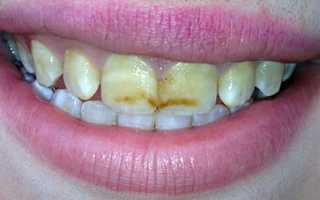

Фото эрозивной, эндемической, штриховой формы

Фото 1. Эрозивная форма флюороза, эмаль значительно истончена, на ней наблюдаются ямки.

- Эрозивная: на зубах располагаются ямки, эмаль особо истончена на жевательной поверхности.

- Эрозивная. Наличие пигментных пятен, множественных эрозий на поверхности зуба.

- Деструктивная. Истирание эмали, нарушение формы коронки из-за эрозий.